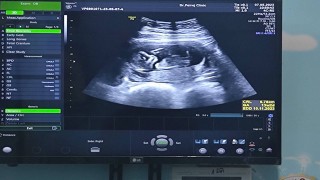

ภาพอัตราซาวด์12วีค

อันนี้ไม่ได้ซาวด์ตอน 12 วีค นะคะเเต่พอดีว่าเข้าไปหาในกูเกิลค่ะ เขาบอกว่าเราจะรุ้เพศลูกตอนประมาณ 18 - 21 วีคค่ะ

12สัปดาห์ ยังไม่รู้เพศค่ะ หมอนัดสิ้นเดือนมิถุนา น่าจะได้ลุ้นเพศ ถ้าน้องไม่หนีบ🥰🥰

บ้านนี้ซาวทุกเดือนเลยค่ะ 12 วีคยังไม่เห็นเพศเลยค่ะ

ตอน 12 week ยังไม่ทราบเพศค่ะ มาทราบตอนผล NIPT ออก😊